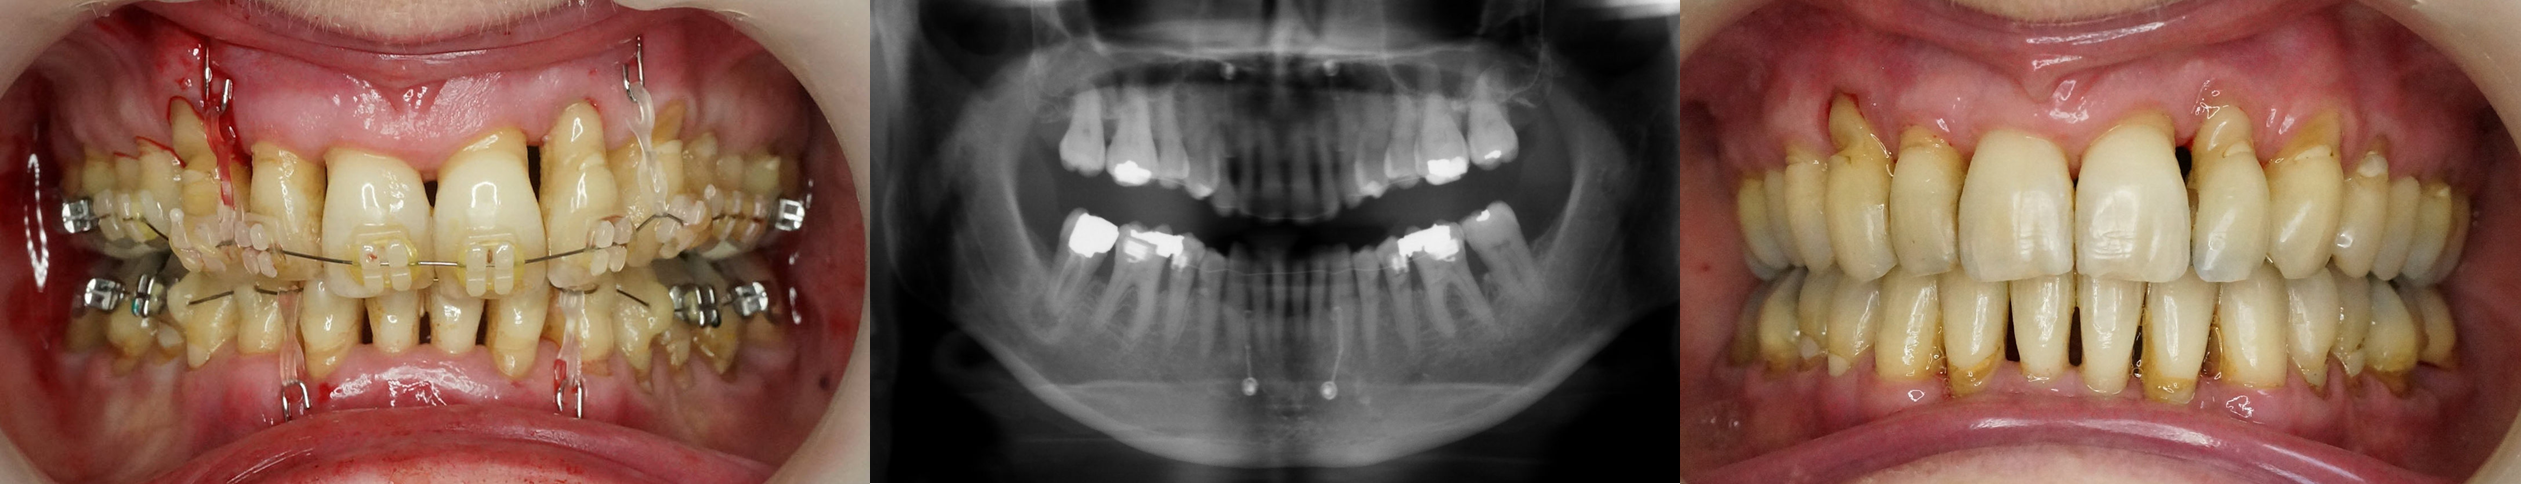

Kit Ingression incisive (2 vis + 2 CTO).

L'implantation se fait de chaque côté de la symphyse mandibulaire.

Pliage d’un crochet pour fixer une ligature élastique reliée à l’appareil orthodontique. Elle devra être remplacée périodiquement.

Le fil devra parfois être raccourci au cours de l'ingression.

Les incisives +/- canines sont ingressées.

Une tendance à la vestibulo-version coronaire existe naturellement, elle devra être contrôlée.